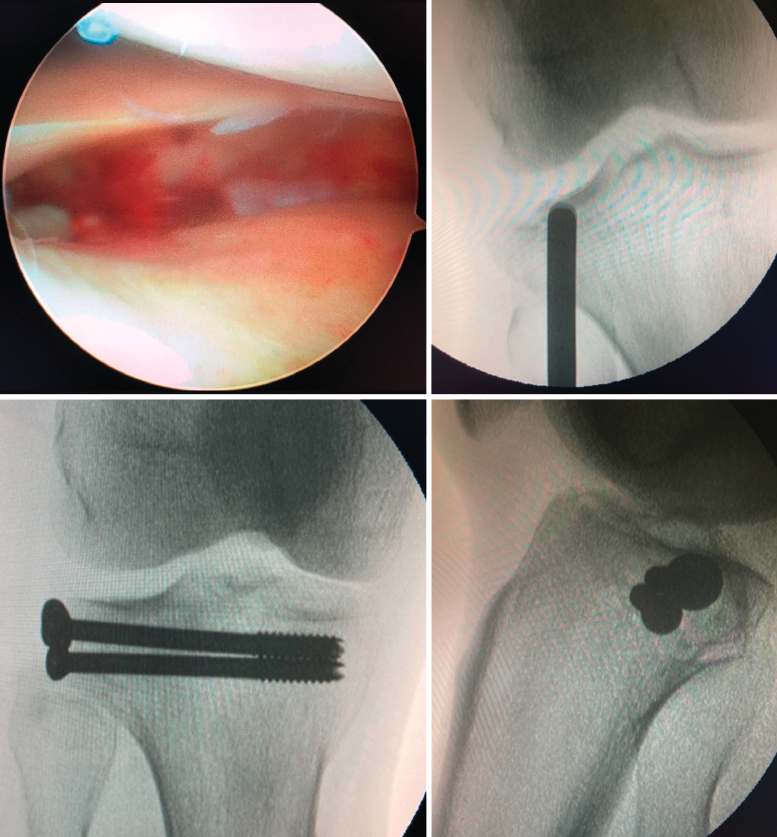

Como ya hemos señalado anteriormente, el uso de la artroscopia de rodilla como asistente quirúrgico ha mejorado en gran medida la reducción articular de estas fracturas y el tratamiento de las lesiones asociadas intraarticulares. Está especialmente indicada en fracturas de tipo I, II y III de Schatzker, que también sintetizaremos con placas de sostén o tornillos canulados con aporte o no de injerto óseo o algún tipo de sustitutivo óseo. La técnica se realiza a través de los portales artroscópicos clásicos anterolateral y anteromedial, y con manguito de isquemia en el muslo. Inicialmente, se drena el hematoma para pasar después a la retirada de cuerpos libres, la evaluación de la superficie articular y el diagnóstico de lesiones meniscales y ligamentosas. Si existe hundimiento articular, se puede emplear una aguja de Kirschner a mano alzada o con ayuda de la guía de reconstrucción del ligamento cruzado anterior desde la cortical tibial hasta en centro exacto del hundimiento de la fractura. Posteriormente, se realiza un túnel tibial a través del cual podemos introducir un dilatador o botador para llevar la superficie articular a la altura adecuada, todo esto bajo visión intraarticular directa y control radioscópico (Figura 4).

Figura 4. Fractura de Schatzker III tratada mediante reducción cerrada asistida con artroscopia y osteosíntesis con 2 tornillos canulados de 6,5 mm.